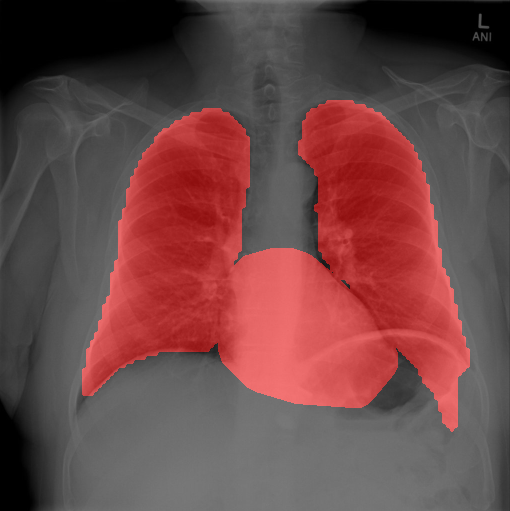

4.2.1 Cardiomegaly Localization

The localization of abnormalities in cardiomegaly examples are shown in Fig. 7. Here, of the image area is shown which has the highest sensitivity. It can be observed from the figures that the network is indeed most sensitive to the region where the heart is larger than a normal heart. We have performed this experiment on cardiomegaly and normal images and found this localization to be consistent for most examples. There is not much functional difference between a normal and cardiomegaly example other than the fact that the heart in cardiomegaly is larger than a normal heart. Given the fact that the normal images could also have various size of heart depending on the age or physical attributes of a patient, we found this level of localization sensitivity to be remarkable. Also interesting is the fact that the standard rule based features like CTR and CTAR take into account the relative size of heart and lung to determine if there is cardiomegaly present or not. In the DCN localization experiment, we see counter-intuitively that most of the signals contributing to the softmax score are coming from the heart only. This means that there are characteristic features in the shape of the heart and its surrounding regions that alone is sufficient to detect cardiomegaly. The lung and its relative size are probably less important features when trying to detect cardiomegaly. This observation is counterintuitive and needs to be explored further in future work.

In this section we show more examples of localization. Few localization samples are shown in Fig. 11. It can be observed that, in the CXRs with Cardiomegaly (Fig. 11(a) and (b)) a fine localization around the heart is observed. In the normal CXRs (Fig. 11(c) and (d)) such localization is not observed. Rather the lowest probabilities are spread out in the CXR image. It is interesting to note that, the localization algorithm gets low probability where the heart is enlarged during cardiomegaly, but the proportion is small compared to the localization in other areas of normal CXRs. In order to observe the performance of the heat map we computed histograms of heat maps of each of the 100 CXRs in the test set for Cardiomegaly detection and average histograms are shown in Fig. 11(e) and (f) for CXRs with Cardiomegaly and normal CXRs, respectively. It is to be noted that, the histograms include both success and failure cases. It can be observed that, for CXRs with Cardiomegaly the classifier is highly sensitive toward Cardiomegaly detection even under occlusion. This indicates that, the classifier primarily looks for local features in a CXR instead of some feature that is spread out in the entire CXR. However, the classifier is not sensitive toward normal CXRs under occlusion. Rather, the probabilities are spread out in the probability spectrum. After that, we analyzed the failure cases where the classifier is unable to classify the image correctly. Two such examples of failure cases are shown in Fig. 12. The localized CXR shown in Fig. 12(a) contains Cardiomegaly whereas the classifier detects it as normal. However, the localization shows that it localizes around heart quite well despite the in accurate classification. On the other hand, Fig. 12(b) shows an example of normal image which has been classified as Cardiomegaly by the classifier. There is stronger localization around the hear that that is observed for normal images as in Fig. 11(c) and (d), however, like those images the localization is spread out.